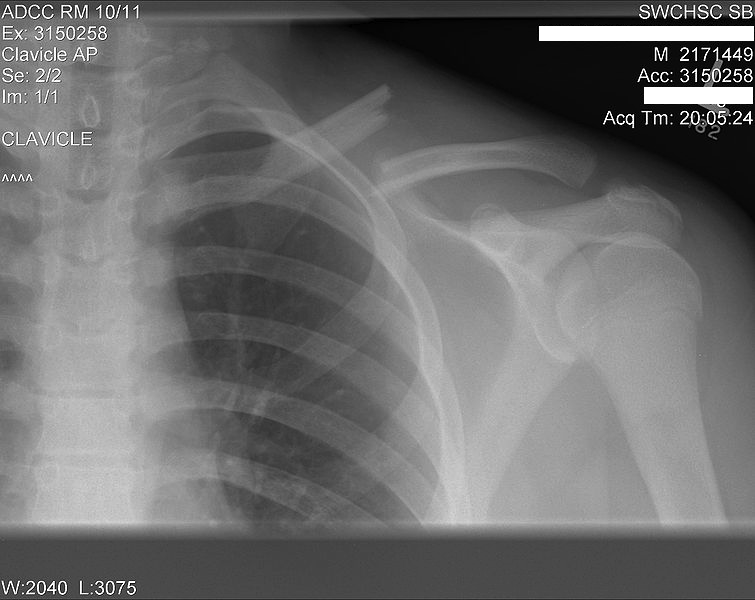

This is what a broken collar bone looks like. Nuclear Medicine, Med Locked Collar Bone Your clavicle (collarbone) is a long, slightly curved bone that connects your arm to your body. the collarbone, also known as the clavicle, connects the shoulder blade to the breastbone. Common causes of a broken. Apply ice packs to your collarbone for 15 minutes at a time, up to four times daily, to reduce swelling. collarbone pain can. Locked Collar Bone.